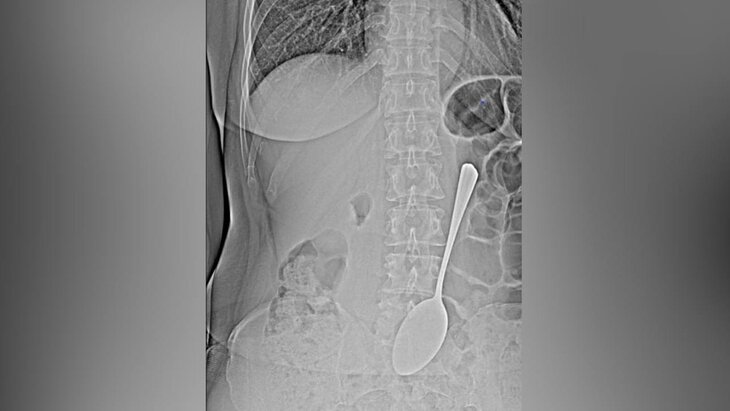

Фото: телеграм-канал "БСМП|Бурятия"

Бурятские врачи больницы скорой медицинской помощи имени В. В. Ангапова спасли женщину со столовой ложкой в желудке. Об этом сообщает "Газета.ру" со ссылкой на пресс-службу медучреждения.

Врачи использовали эндоскоп и специальные инструменты, чтобы извлечь из пациентки столовую ложку, не прибегая к сложной хирургической операции. Отмечается, что такие крупные инородные тела могут провоцировать кишечную непроходимость или перфорацию желудка.

После того как врачи вытащили ложку, пациентку отправили домой. Женщина так и не объяснила, как инородный предмет попал внутрь ее желудка.